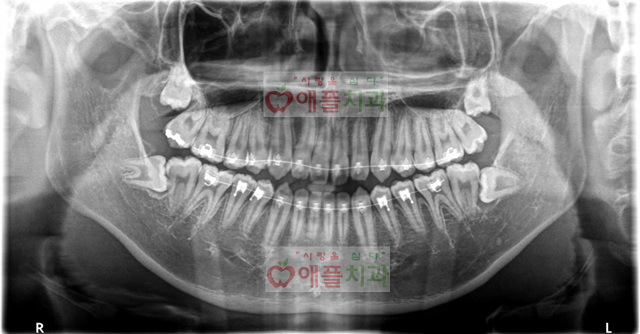

<처음 내원시>

시내 유명한  oo 교정 치과에서 수술적 사랑니 발치 의뢰된 환자입니다.

내원 당일날 좌측 상, 하 사랑니 발치 하였습니다.

1주일뒤 실밥 제거하면서 반대측 상, 하 사랑니 발치 하였습니다.